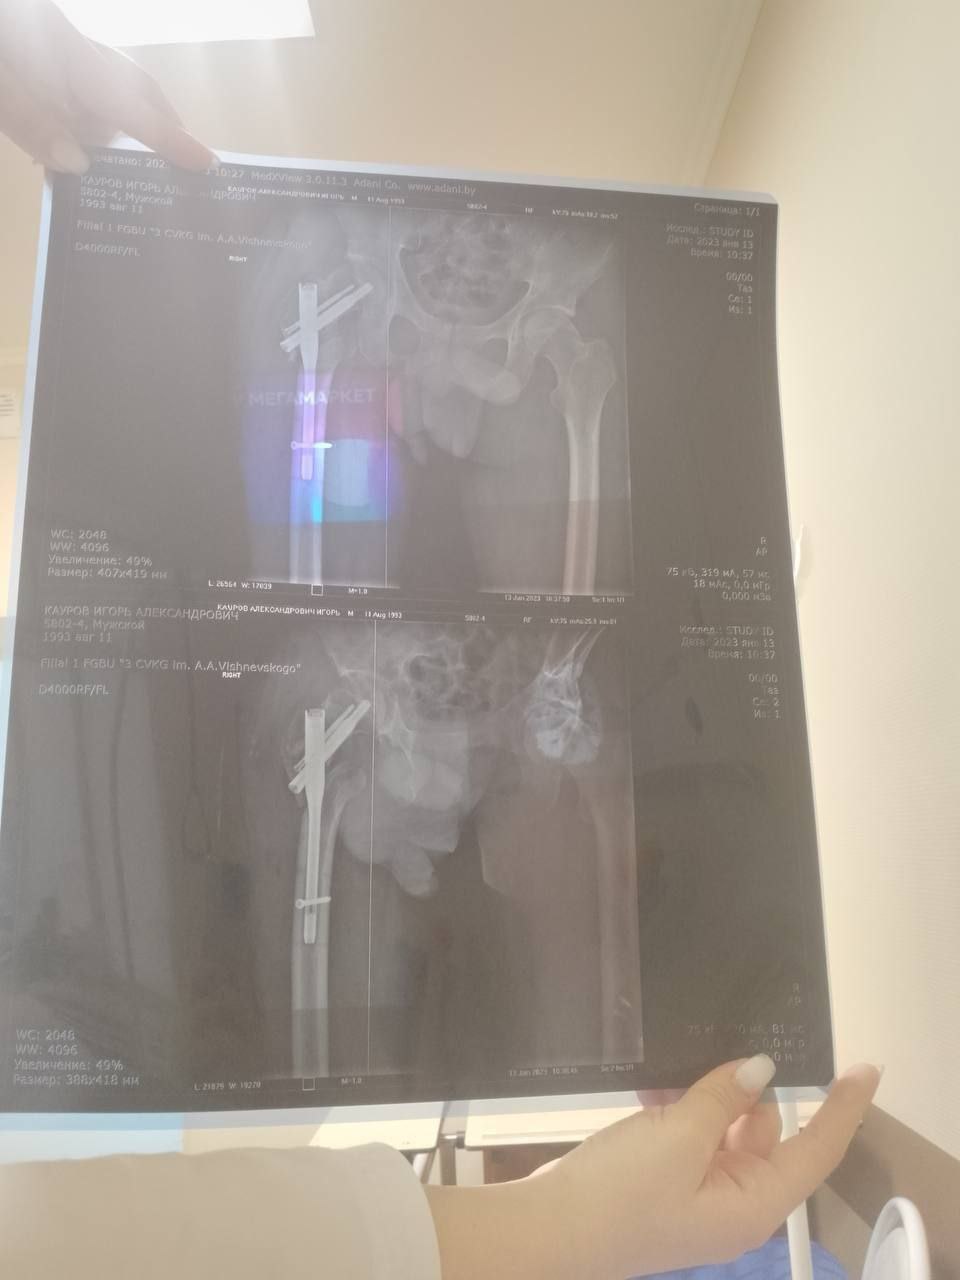

Пациентом стал 32-летний Илья из ЛНР, мобилизованный 25 февраля 2022 года.Сержант получил тяжелейшее осколочное ранение правого бедра под Херсоном 28 августа 2022 года.За три с половиной года боец прошёл через десять госпиталей, включая ЦВКГ им. Вишневского в Москве и ВМА им. Кирова в Санкт-Петербурге, перенёс множественные операции по удалению некрозов и остеосинтезу.

К моменту увольнения со службы в июле 2024 года основная проблема оставалась нерешённой: правая нога была короче левой почти на 9 сантиметров. Стандартное протезирование в такой ситуации неэффективно.

Хирургам ЛРКБ предстояло работать в рубцово-изменённых тканях после десятка предыдущих вмешательств, устранить очаги инфекции и с помощью специальных ревизионных компонентов восстановить биологическую ось конечности и вернуть ей физиологическую длину.